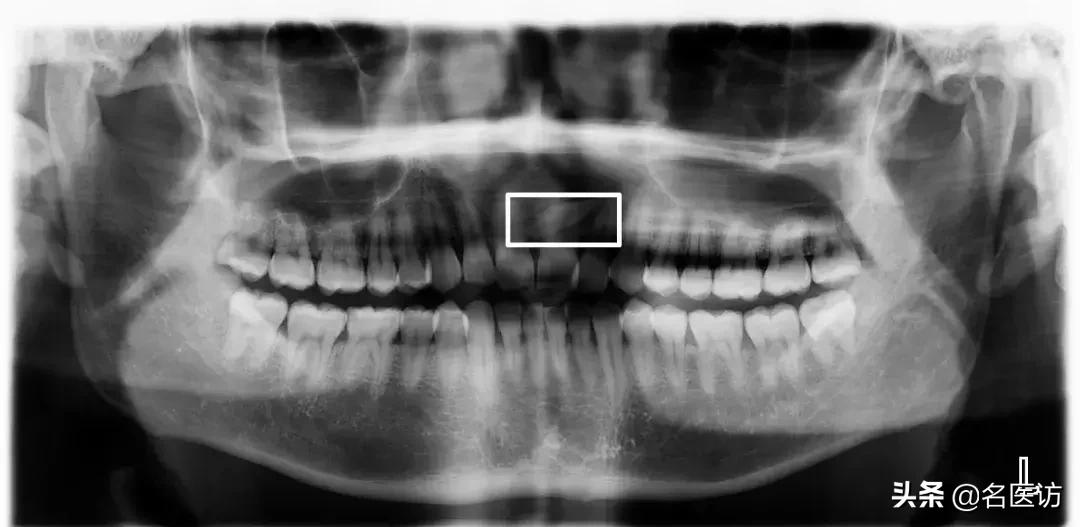

4、上颌窦

上颌窦底与上颌后牙牙根的位置关系也是矫正时要重点关注的,一般来说上颌第一磨牙与上颌窦底距离最近,但两者依然保持着“睦邻友好”的关系,如果上颌牙的某些牙根进入了上颌窦内,那么这些牙齿在矫正时移动的阻力可能会比其他牙齿大很多,可能存在这些牙齿的矫正效果不如预期的情况。另外,即使这些牙齿可以移动,但也会增加牙根吸收、牙齿移动不了的风险。

牙根穿过上颌窦